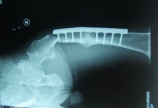

病例男性,56岁股骨干骨折术后5年愈合不佳,行走是摔伤致钢板近端再次骨折。在本次骨折前大腿行走无疼痛。 1 现在内固定选择长锁定板或髓内针? 2以前愈合不佳的骨折端做不做植骨处理。